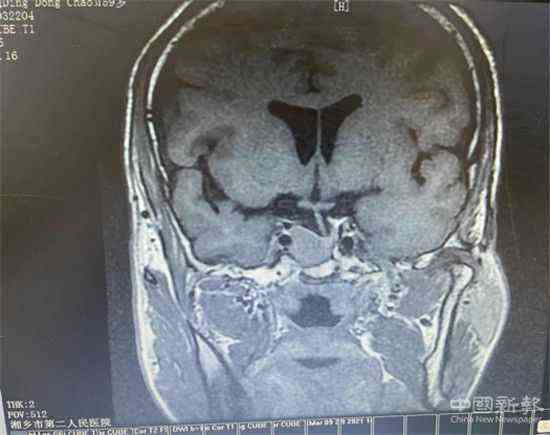

患者的垂體MRI彌散+動態(tài)增強影像資料

據(jù)了解,患者丁某有兩年的糖尿病病史,于2021年3月1日慕名來該院代謝內(nèi)分泌科住院治療。住院期間,丁某在血糖水平高的同時,還伴有甲狀腺功能亢進。但其檢測結(jié)果卻不符合常見的原發(fā)性甲狀腺功能亢進表現(xiàn),呈TSH不適當(dāng)分泌,引起了張云林主任的高度重視。他認為很有可能是腦垂體方面的問題或者甲狀腺激素不敏感綜合征。因此,建議患者進一步做垂體的核磁共振彌散+動態(tài)增強、垂體功能檢測等針對性檢查,以確定病情。但患者因檢查費用等方面的顧慮,不同意進行針對性檢查。本著對病人高度負責(zé)的態(tài)度,張主任多次與患者耐心溝通,并積極向院方申請經(jīng)費支持,全面打消患者各方面顧慮。在醫(yī)院和醫(yī)療團隊的努力下,丁某接受了相關(guān)檢查。結(jié)果顯示:在患者蝶鞍處發(fā)現(xiàn)一較大的垂體腫瘤。結(jié)合臨床及其他輔助檢查,支持垂體TSH瘤這一診斷。